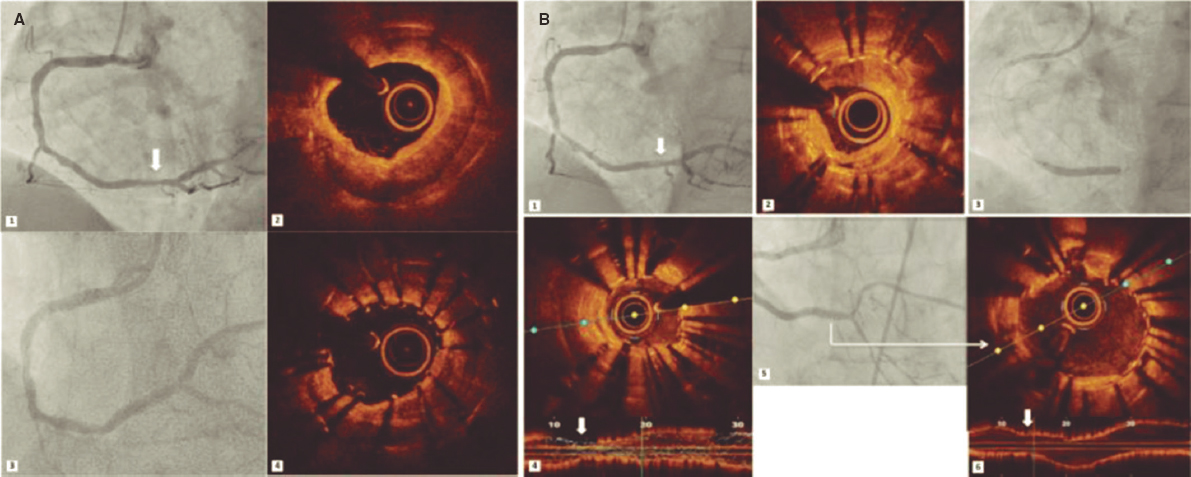

The intravascular ultrasound (IVUS) is useful when the entry site is ambiguous and there are no references to position the guidewire. A lateral branch is required to place the guidewire and IVUS. In these cases, the Slipstream technique38 is very useful. It consists in placing a dual-lumen micro-catheter (DLM) behind the IVUS above the branch guidewire. This increases tremendously the strength exerted with the guidewire that exits the DML lateral port providing better torque and grip (figure 3). The IVUS shows where the occlusion of the vessel is in order to navigate the guidewire (of high-gram, directivity, and torque-response) towards that point (figure 4).

Figure 3. The occluded vessel is at the 6 o’clock position approximately (A) as the guidewire is moving towards the occlusion (B, C and D).

Figure 4. The catheter of intravascular ultrasound in the subintimal space is between the 9 and 12 o’clock positions and true lumen between the 3 and 9 o’clock positions.